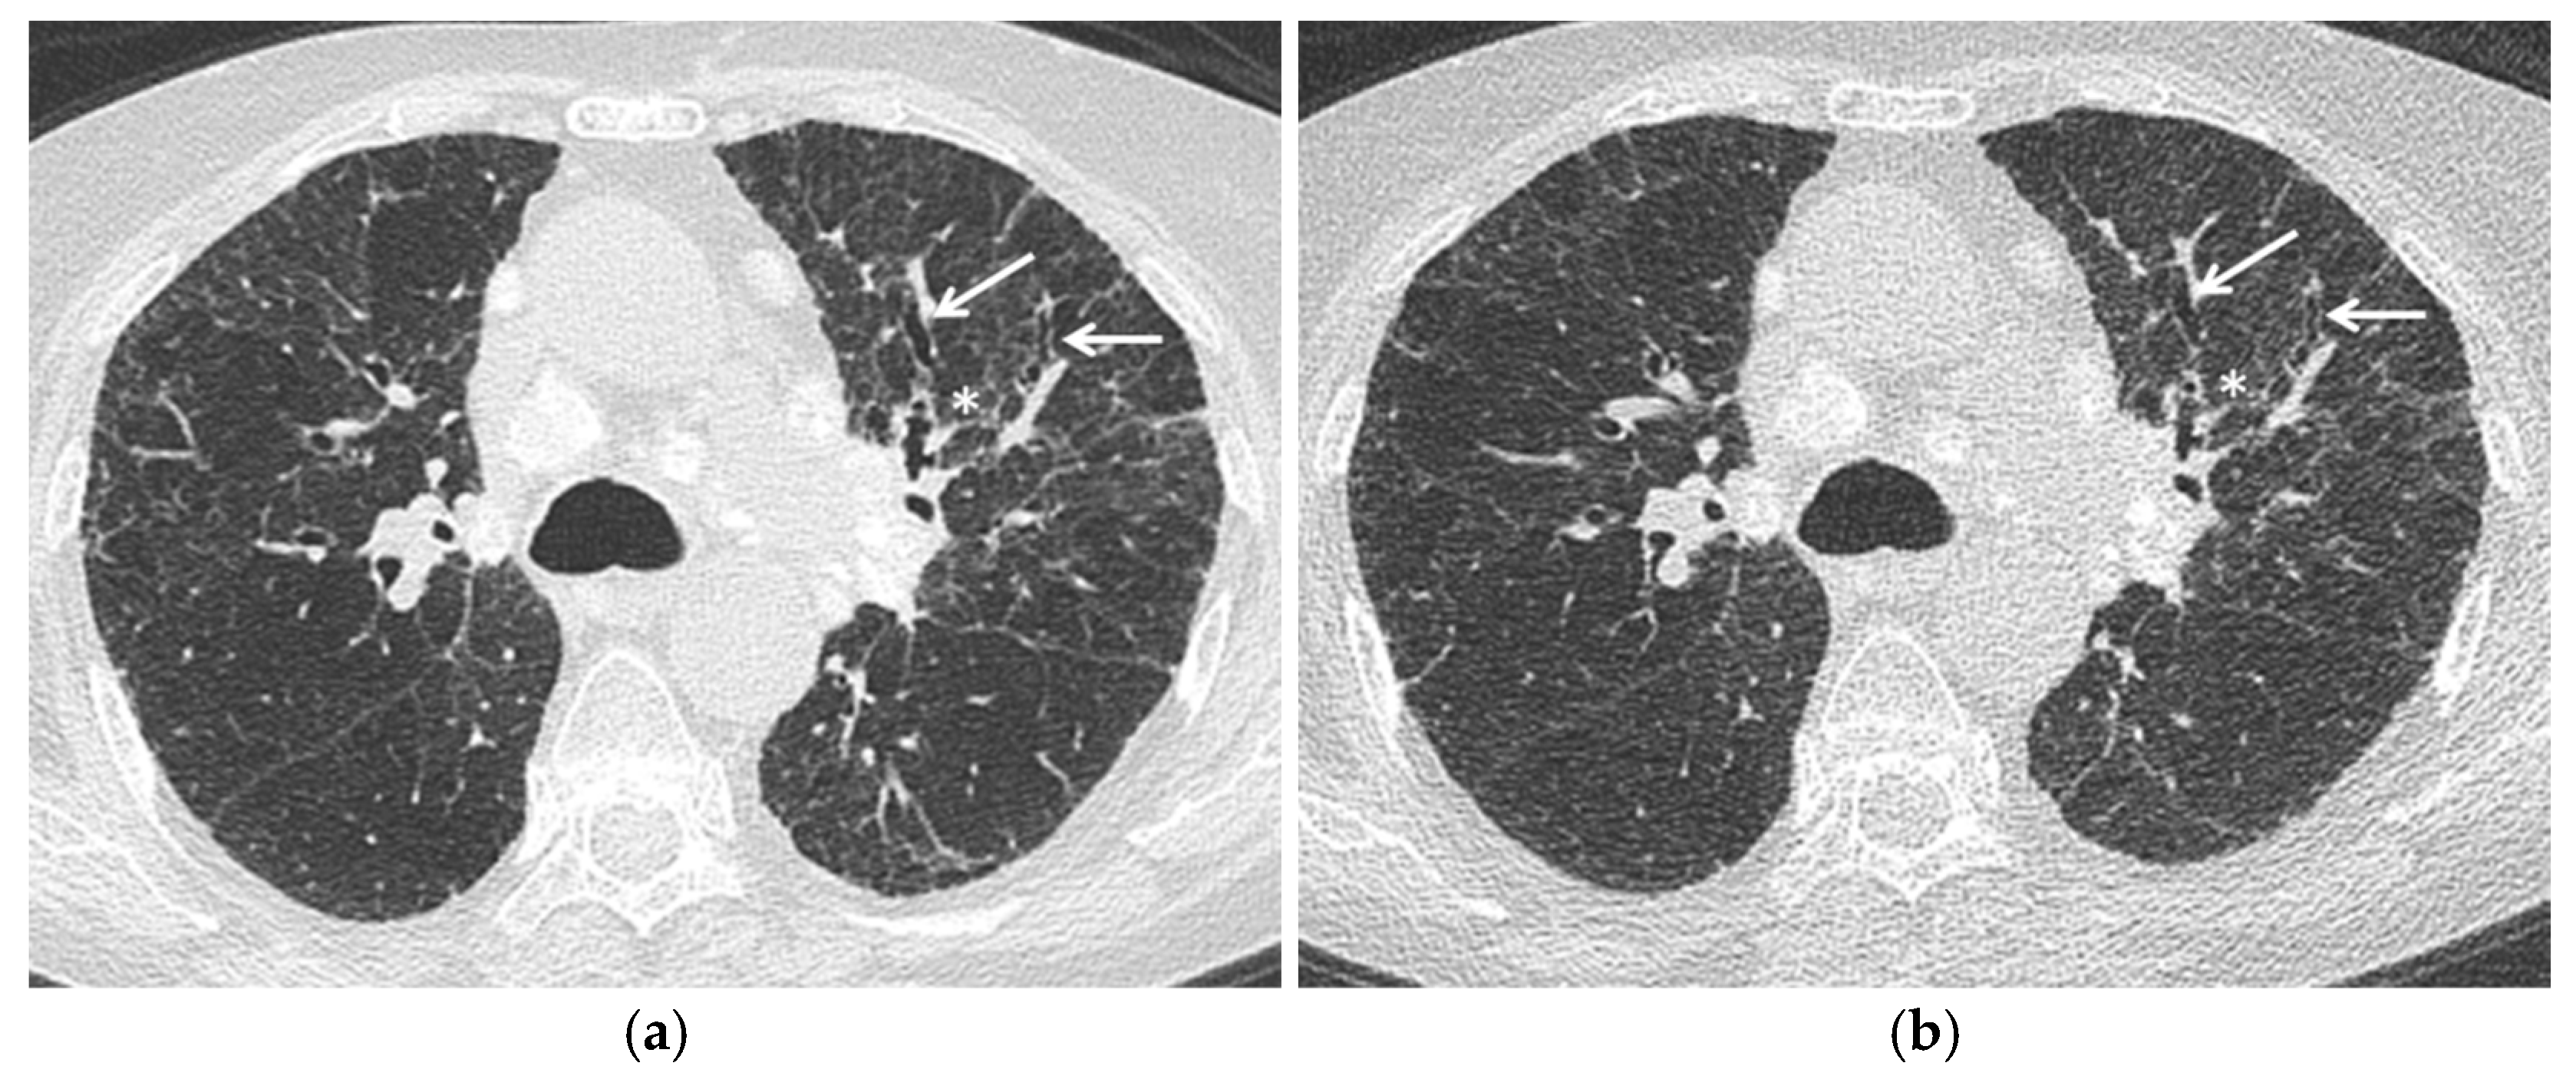

Since the potential advantages described above and the need to keep the radiation exposure as low as possible, studies are needed to validate these radiation-saving techniques in sarcoid patients, in particular in disease monitoring and, although uncommon, in children (Figure 1).

Figure 1.

Stage IV pulmonary sarcoidosis. Comparison between (a) standard chest HRCT acquisition (effective dose 3.3 mSv) and (b) Ultra-low dose acquisition (effective dose 0.8 mSv) with a 75% radiation dose reduction. Fibrotic changes—specifically irregular interstitial thickening (asterisk) and traction bronchiectasis (arrows)—are clearly evident at Ultra-low dose acquisition. Mediastinal calcified lymph nodes are also evident.